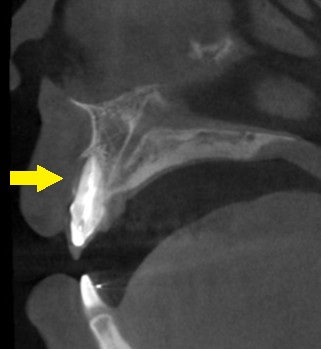

CTで見ると、この歯の唇側の骨が吸収されて、膿も出ていると思われました(下の写真下段左)。

おそらく、歯根の側方に亀裂か、穴が空いていて、歯根の治療では細菌が完全に排除できないためではないかと考えられました。